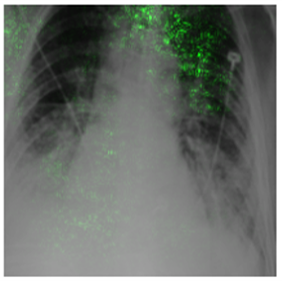

Deep Learning of neural networks has progressively become more prominent in healthcare with models reaching, or even surpassing, expert accuracy levels. However, these success stories are tainted by concerning reports on the lack of model transparency and bias against some medical conditions or patients' sub-groups. Explainable methods are considered the gateway to alleviate many of these concerns. In this study we demonstrate that the generated explanations are volatile to changes in model training that are perpendicular to the classification task and model structure. This raises further questions about trust in deep learning models for healthcare. Mainly, whether the models capture underlying causal links in the data or just rely on spurious correlations that are made visible via explanation methods. We demonstrate that the output of explainability methods on deep neural networks can vary significantly by changes of hyper-parameters, such as the random seed or how the training set is shuffled. We introduce a measure of explanation consistency which we use to highlight the identified problems on the MIMIC-CXR dataset. We find explanations of identical models but with different training setups have a low consistency: $\approx$ 33% on average. On the contrary, kernel methods are robust against any orthogonal changes, with explanation consistency at 94%. We conclude that current trends in model explanation are not sufficient to mitigate the risks of deploying models in real life healthcare applications.